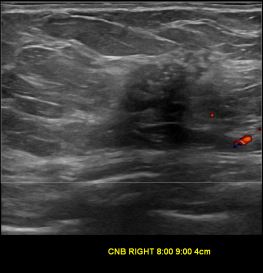

상기환자는 우측 유방 만져지는 멍우리로 내원하신 60대초반 여성분으로 의심스러운 우측혹 조직검사 시행해 제자리암으로 진단되었습니다